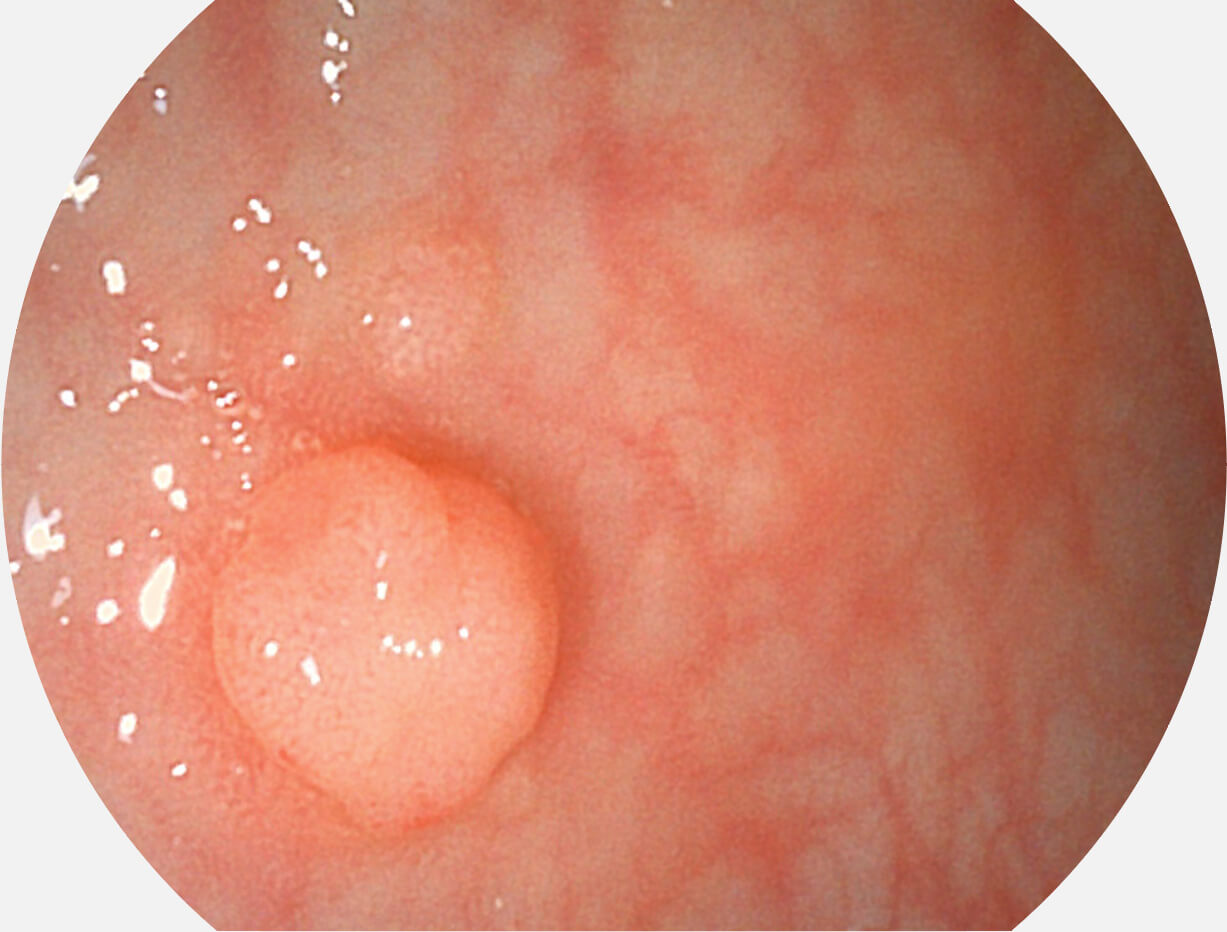

白光图像

SFI图像

采用光路合束技术,光谱自由度高,实现了更丰富的照明模式,染色模式SFI及VIST,从远景到近景,助力消化道早期疾病诊断。